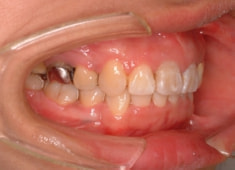

右下7番欠如歯(保存不可能歯につき抜歯)右下8番利用

治療開始時